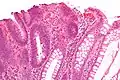

| Adénome dentelé sessile | Semblable à hyperplasique avec hyperserration, bases des cryptes dilatées/ramifiées, des cellules de mucine apparents à la base des cryptes | Oui | ![]() |

||

| Adénome tubulaire (villositaire, tubulovilleux) | Glandes tubulaires avec des noyaux allongés (au moins à faible teneur atypie) | Oui | ![]() |